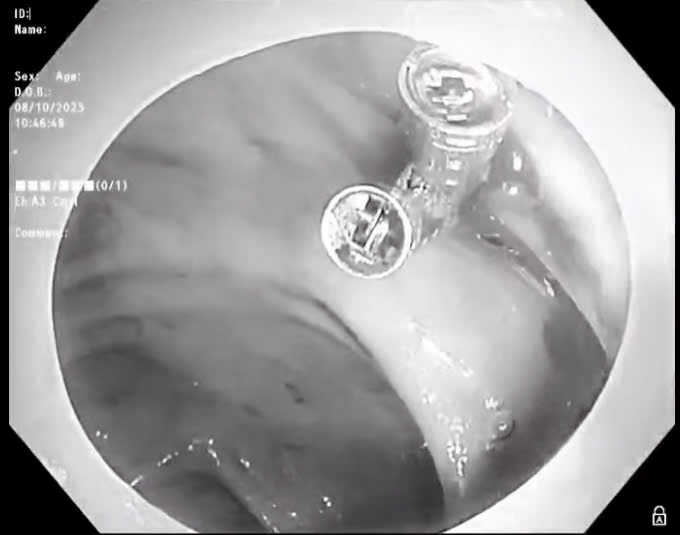

Ngoài ra, bệnh viện Trường Đại học Y Dược Huế cũng đang là một trong những đơn vị dẫn đầu khu vực miền Trung - Tây Nguyên về số lượng dịch vụ kỹ thuật được áp dụng trong khám, chữa bệnh.